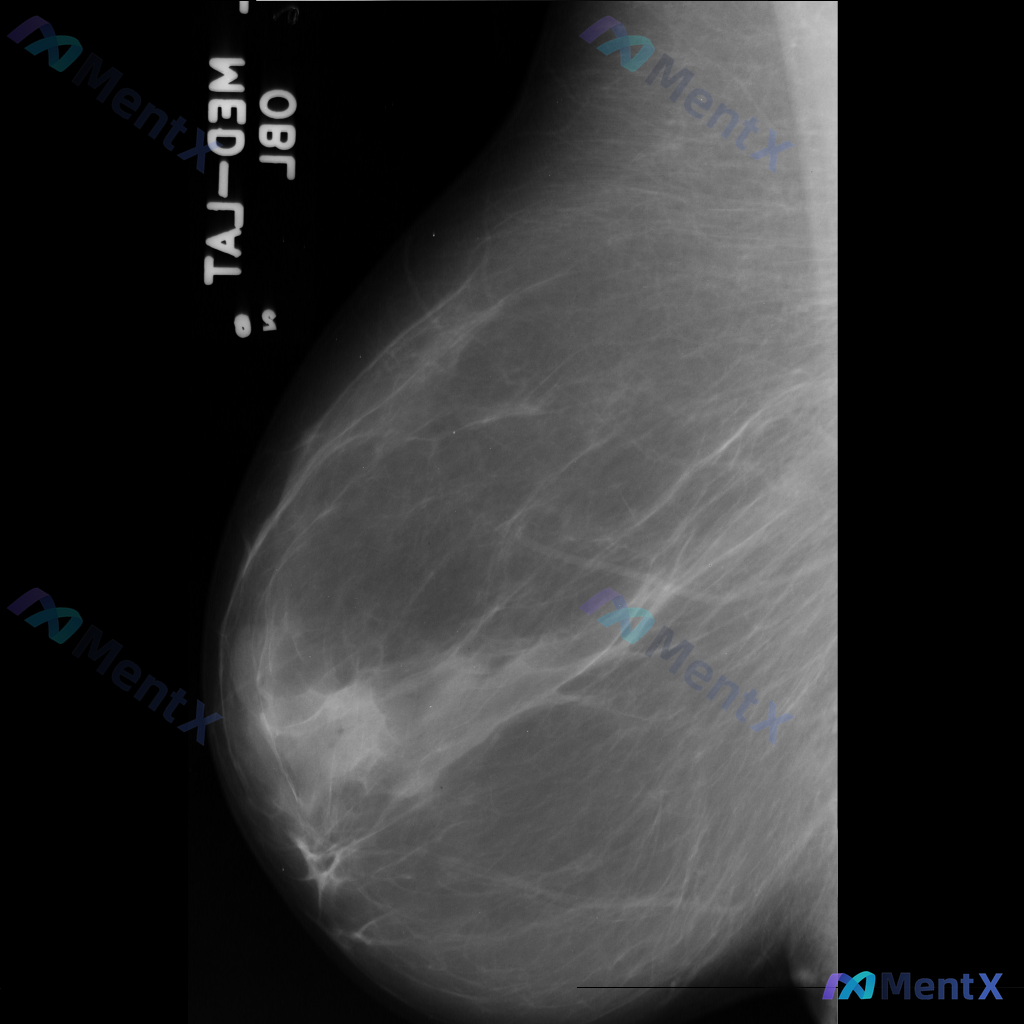

整理到一张乳腺钼靶影像的读片资料,想和大家讨论一下读片思路: 影像里能看到的主要异常是乳腺内结构扭曲(正常导管小叶结构有集中、牵拉、不规则向中心汇聚的表现,但没有明确肿块),同时还有不对称致密影(局部组织密度增高,和周围或对侧分布不太一致)。另外,乳腺本身纤维腺体组织偏多,可能属于 BI-RADS...

整理到一份乳腺钼靶影像资料,主要表现如下: - 乳腺中后部可见局灶性结构扭曲 - 无明确的肿块核心 - 周围腺体和脂肪界面被不规则牵拉 目前暂不提供既往影像对比和详细病史(手术史、外伤史、炎症史等)。 这种表现大家会先怎么判断?更倾向于往哪种方向考虑?

整理到一份乳腺钼靶的影像资料,想和大家讨论一下: - 钼靶所见:左侧乳腺中央偏下区域存在局限性结构扭曲,表现为纤维腺体组织排列紊乱、牵拉;未见明确的肿块或钙化灶。 - 背景:乳腺密度较高,属于不均匀致密型或极度致密型(ACR B或C型)。 目前这种结构扭曲的表现,大家会先往哪个方向考虑?下一步的评估...